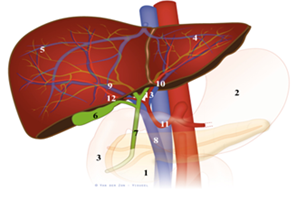

Figuur 4: 1. alvleesklier, 2. maag. 3. 12-vingerige darm, 4. lever links, 5. lever rechts, 6. galblaas, 7. hoofdgalweg, 8. poortader, 9. poortader rechts, 10. poortader links, 11. lever slagader, 12. lever slagader rechts, 13. leverslagader links. Bron: Amsterdam UMC

De lever zelf bestaat uit 2 delen. Een linker helft en een rechter helft (zie figuur 4). Elk deel bestaat weer uit kleinere delen, segmenten genaamd (zie figuur 5). In totaal heeft de lever 8 segmenten. Ieder segment (deel) heeft een eigen bloedvoorziening en gal afvoersysteem (zie figuur 6).

De lever zelf bestaat uit 2 delen. Een linker helft en een rechter helft (zie figuur 4). Elk deel bestaat weer uit kleinere delen, segmenten genaamd (zie figuur 5). In totaal heeft de lever 8 segmenten. Ieder segment (deel) heeft een eigen bloedvoorziening en gal afvoersysteem (zie figuur 6).